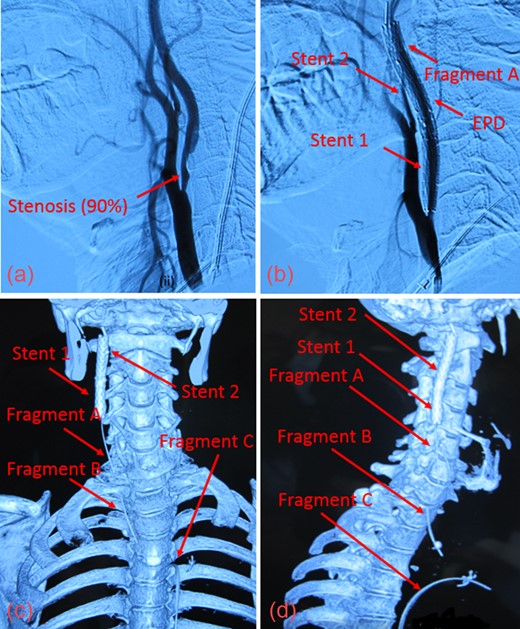

A 57-year-old male in Beijing, China underwent carotid artery stenting via transfemoral approach for severe (>90%) asymptomatic right internal carotid artery (ICA) stenosis (Fig. 1a). A neurosurgical team at an outside facility performed the procedure using a 5-mm SpiderFXTM distal filter EPD and ev3 ProtégéTM 8 × 30 mm RX stent (Covidien; Plymouth, MN, USA). During deployment, this stent (referred to as Stent 1) inadvertently migrated cephalad and became lodged onto the EPD. Despite multiple attempts, the EPD was unable to be retrieved with the capture sheath. The physicians placed another ev3 7 × 40 mm ProtégéTM RX stent in the right ICA to compress the EPD and guidewire against the arterial wall. We refer to this as Stent 2, which was placed at the C1–C2 vertebral level, superior to Stent 1 (Fig. 1b). The patient was discharged on aspirin and clopidogrel, with the retained guidewire sutured in place at the groin. At time of discharge, the ICA stenosis had not been resolved.

(a) Digital Subtraction Angiography of patient prior to angioplasty with 90% stenosis of the ICA. (b) Fractured guidewire when patient presented to our facility. The EPD cannot be clearly seen. (c) Reconstructed CT image in anterior view showing the 3 guidewire fragments (Fragments A, B, C) and the 2 carotid stents (Stent 1 and Stent 2) in the right ICA. (d) Reconstructed CT image in the right lateral view of guidewire fragments and stents.

One month after discharge, the patient began experiencing substernal chest pain radiating to the neck with right suborbital pain. It was discovered that the guidewire had fragmented into three pieces. He was referred to our cardiovascular surgical team at the Anzhen Stroke Center for further management.

Upon presentation, we found moderate (55%) stenosis in the right common carotid artery (CCA) and severe (90%) stenosis in the ICA inferior to Stent 1. The most superior of the three guidewire fragments (Fragment A), still attached to the EPD, was compressed by Stent 2 and extended into the CCA (Fig. 1c and d). The middle piece (Fragment B) was adhered to the right CCA wall by local fibrin deposits. The inferior fragment (Fragment C) extended from the right femoral artery to the thoracic aorta, where it punctured the proximal aortic arch wall (Fig. 2a and b). Thrombus had also formed along the entire 1-meter length of Fragment C.